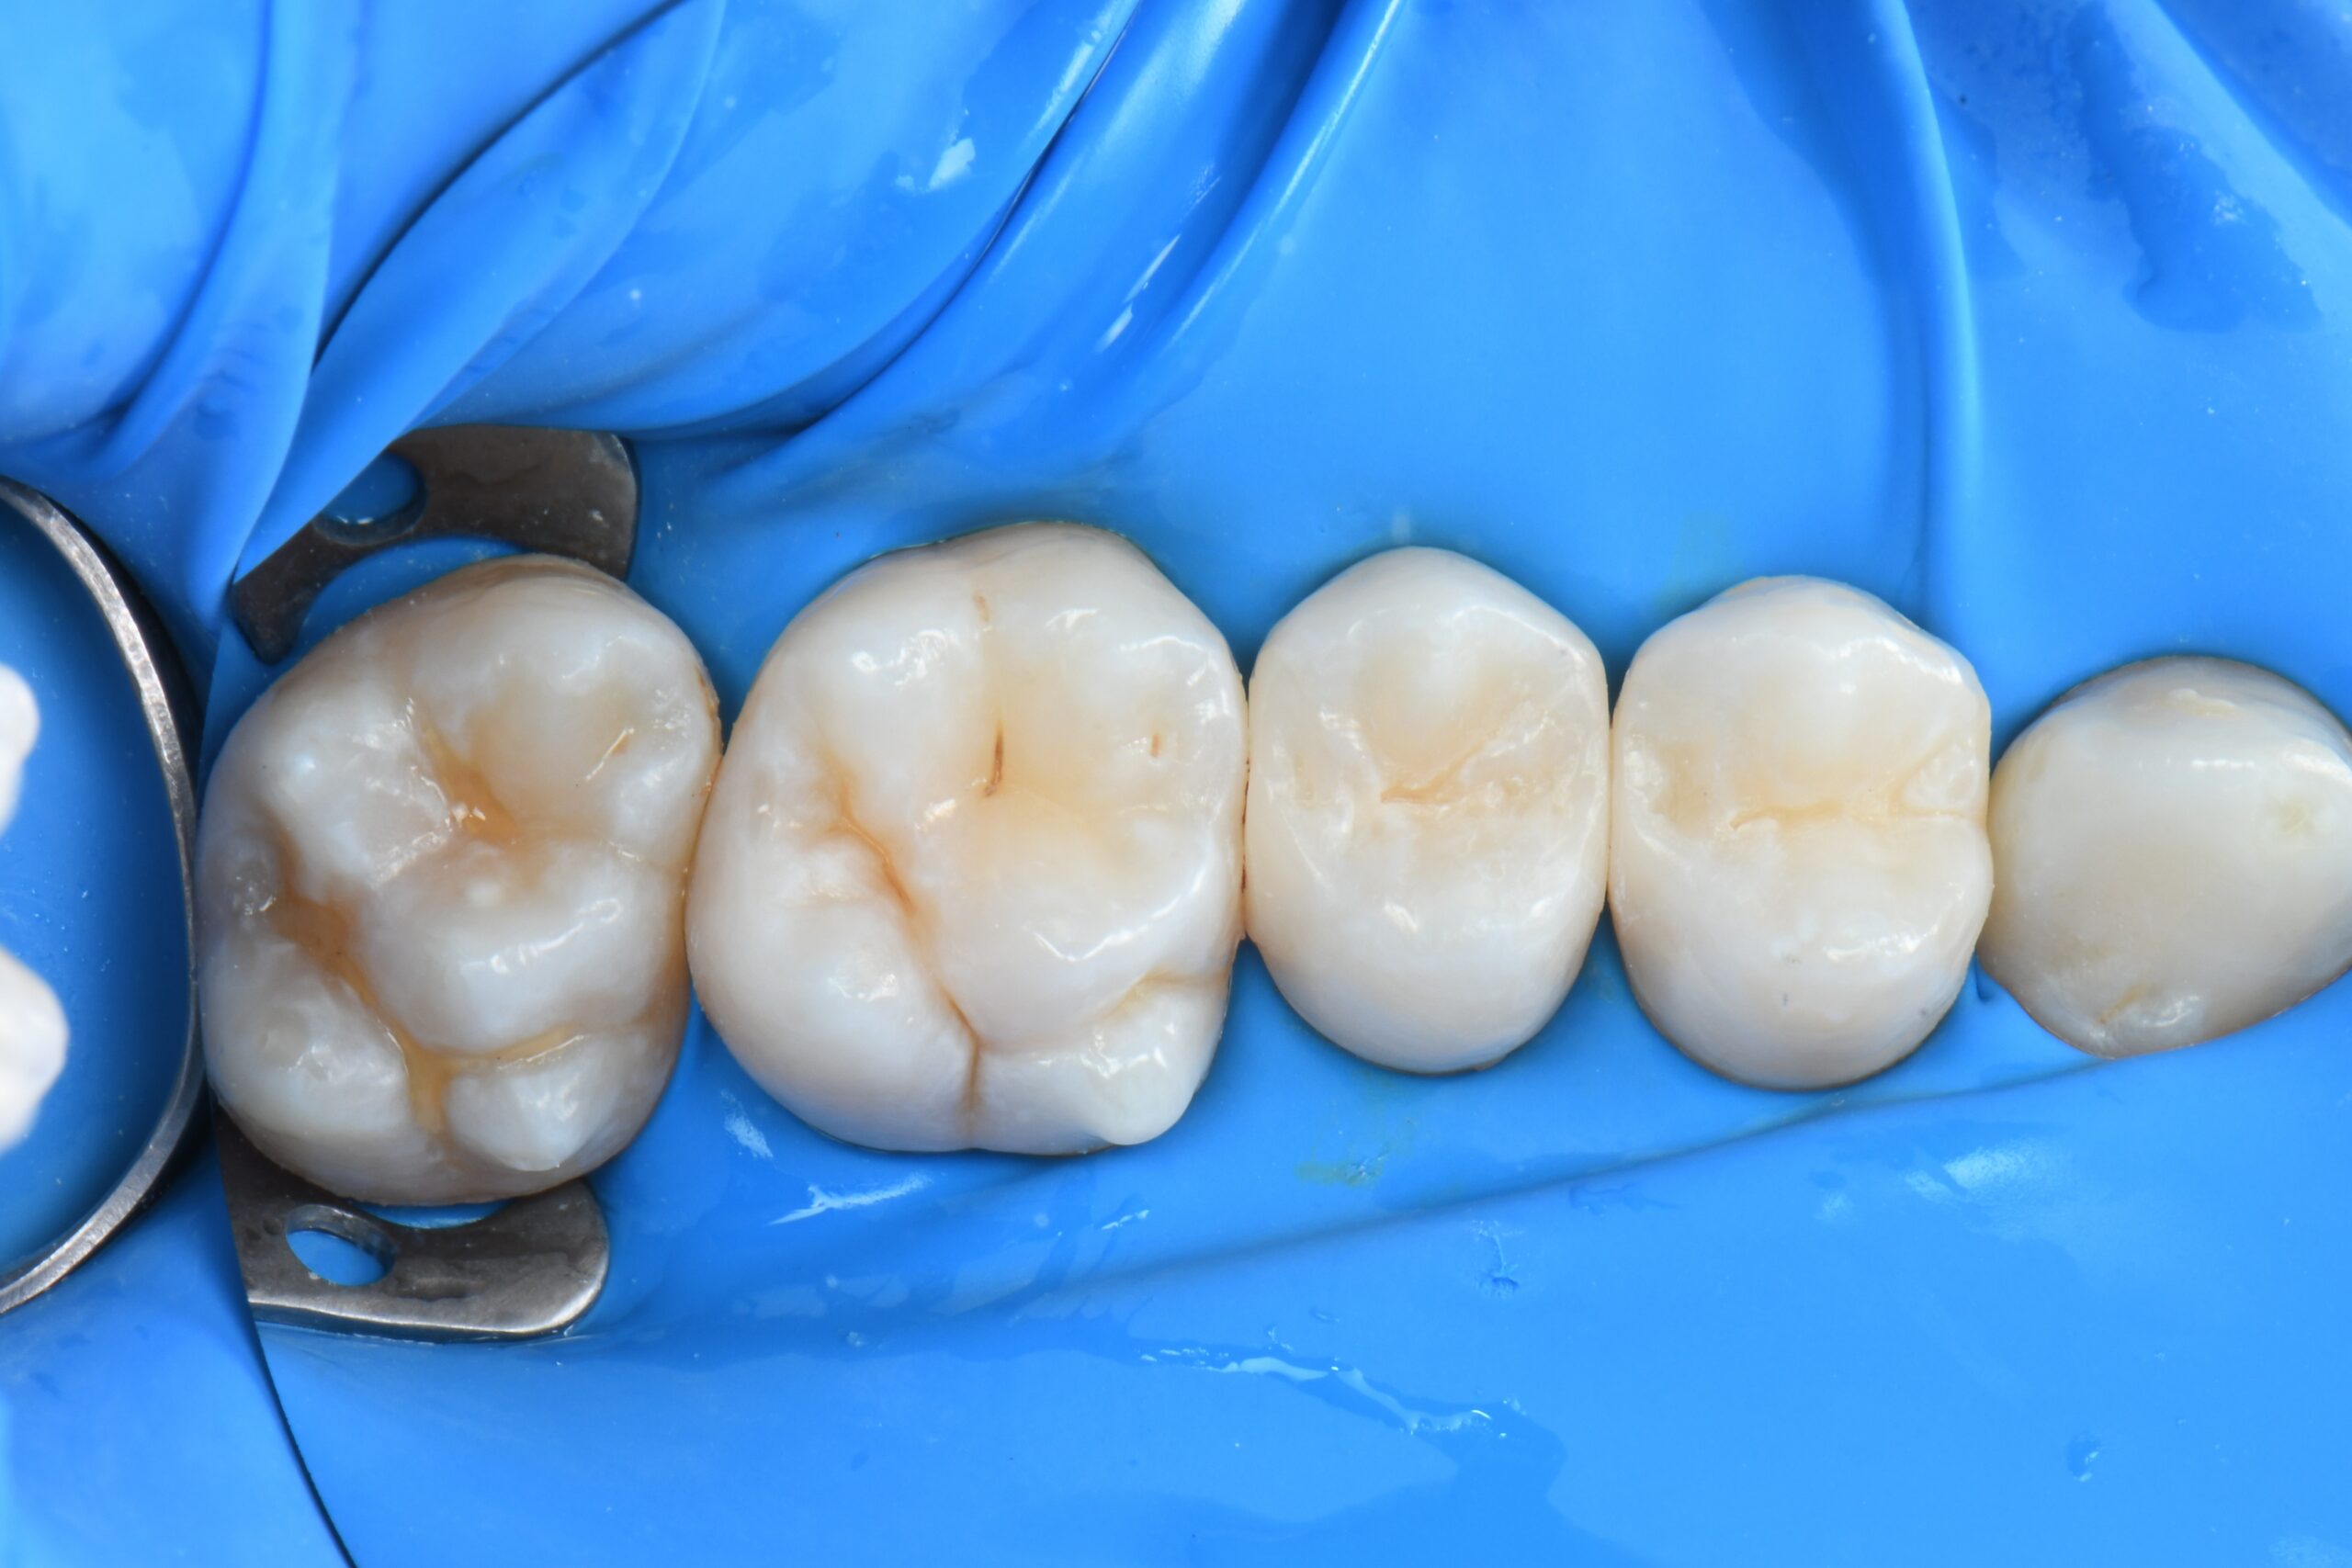

Close-up of six lower molars and premolars with visible occlusal surfaces and surrounding gum tissue

Immediate occlusal post-op photo after rubber dam removal and occlusal adjustments.